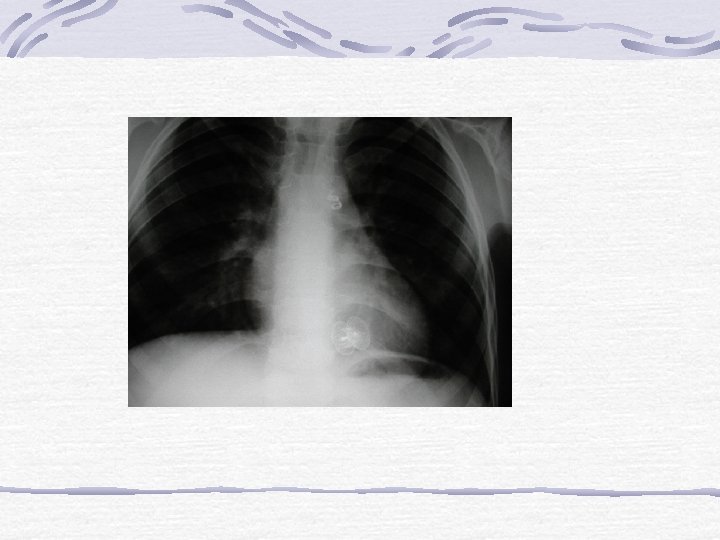

AORT KOARKTASYONU